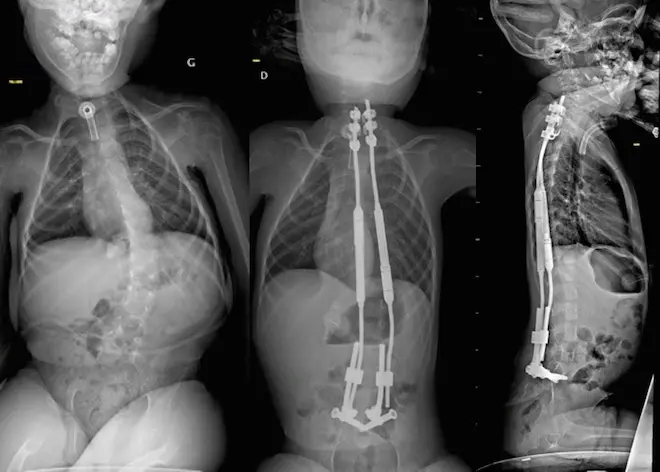

Une scoliose opérée sous assistance robotique

Il s'agissait de poser des vis illio-sacrées et des crochets en haut du dos, reliées par des tiges cintrées pour redresser le dos. La pose des vis de 7mm de diamètre dans un couloir osseux de 8 mm "à proximité des racines nerveuses reste très complexe et rare; elles sont volumineuses au regard de la petite taille des os de l'enfant", précise l'équipe chirurgicale dans un communiqué.

Louis, dont le dos était courbé à plus de 50% et pour qui les corsets et la rééducation n'étaient plus suffisants, peut désormais se rasseoir et dit mieux respirer. Quatre jeunes patients ont depuis bénéficié de ce nouveau type de chirurgie au CHU Amiens-Picardie.